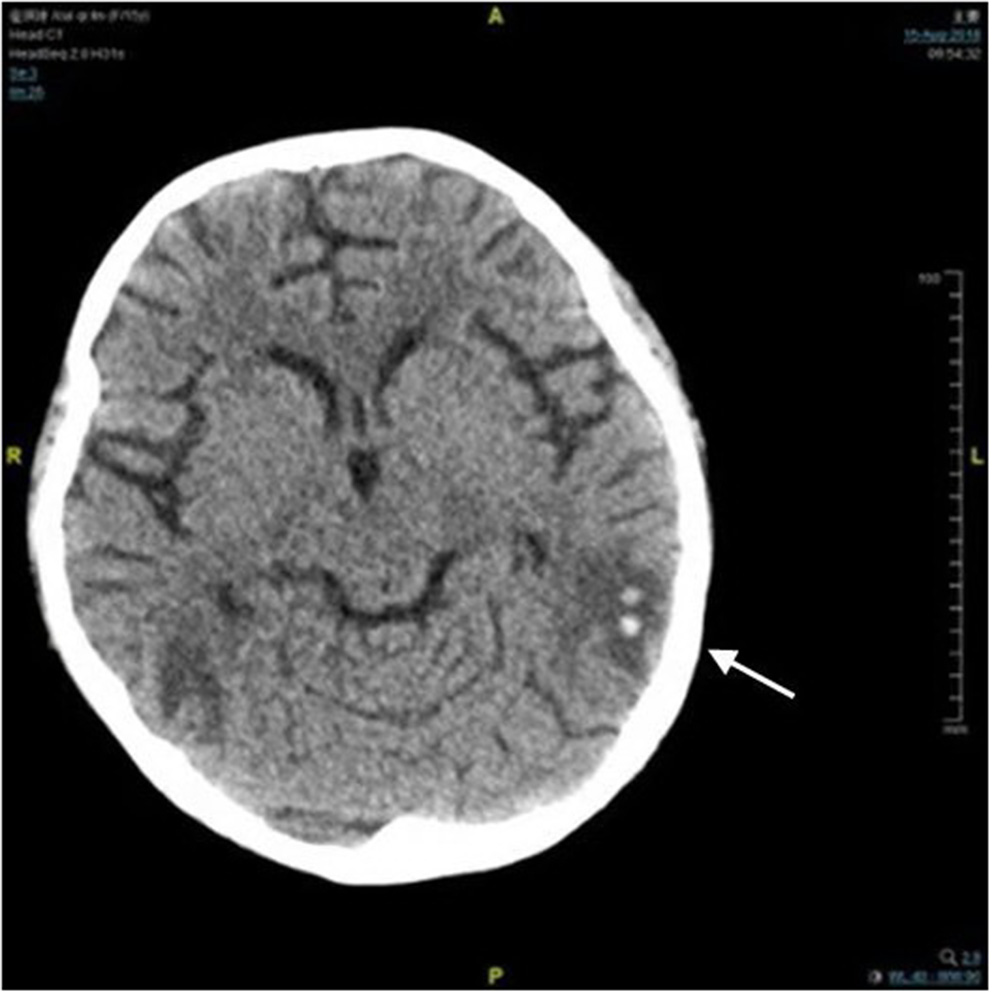

Figure 1

Computed tomography image of brain. There was a small amount of hemorrhage in the left temporal lobe (arrow).